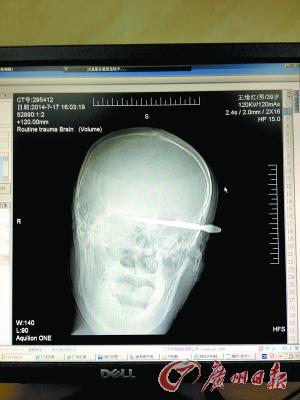

CT影像显示,长条状利器横穿9厘米直达颅底。

利器恰恰从一根大血管和大的静脉窦间穿过。三四小时的手术后,利器被取出时,护士认出来,大叫“呀,是把眉钳!”

这是一把设计成京剧人物造型的眉钳,上端是京剧脸谱,往下是戏服图案,越往下越窄,大约10厘米长。7月17日下午,它精准地插入了一名39岁男子的太阳穴,直达9厘米深的颅底。医生为伤者紧急手术,救回一命。警方从群众处了解到,男子的伤情是由自残造成的。

伤者身上身份证显示他姓王,今年39岁,是湖北荆州人,除此之外,他身上只有100多元,身边没有亲友。由于伤情危急,医院给他马上做了手术。骆锦标说,“医生打开伤者的左边头骨后发现,利器恰恰从一根大血管和大的静脉窦间穿过。利器被取出时,护士认了出来,大叫‘呀,是把眉钳!’”